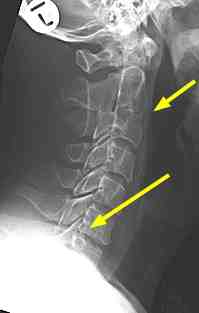

A middle aged man began to experience lower neck, midback pain and tingling in the left arm.

His doctor ordered X-rays. Here's the initial report:

Report I:

Normal vertebral body alignment. No traumatic fracture or dislocation. The intervertebral disc spaces are preserved at all levels with no spondylotic or disc degenerative changes. No subluxation of the verebral bodies. Normal alignment of the spinous processes and facet joints. On the oblique views, the bony neural exist foramina are patent at all levels. The precervical soft tissue is normal.

Radiologist's comment:

Based on the radiologist's report his doctor said there was no need for concern and sent him for physiotherapy.

Aside: Worldwide medical doctors have little training in reading of X-rays so they are reliant on the radiologist's report.

Three months later he first consulted me with serious "hard" neurological findings. Not satisfied with the original report, I asked for a review of the X-rays by another radiologist. Here's his report:

Report II:

Bony alignment is normal. Congenital ankylosis between C2 and C3. Disc spaces are preserved, although the C7-T1 disc is not well shown on the lateral view. Quite large degenerate spurs encroach on both C6-C7 foramina. These arise from the uncovertebral joints. If superadded disc protrusion is suspected an MRI scan may be of help. No cervical ribs.

Notice that the first radiologist missed two important facts:

How reliable are x-rays in diagnosing the source of tingling in arms and hands?

The left oblique view below show the large degenerate spur emerging from the UncoVertebral joint Luschka ... see how it's invading the foramen. The nerve root takes up about half the space in the IVF (inter vertebral foramen) so any tissue that is "space-occupying" will threaten the nerve root.

The right foramen shows how these degenerative changes are occurring in the opposite side also.